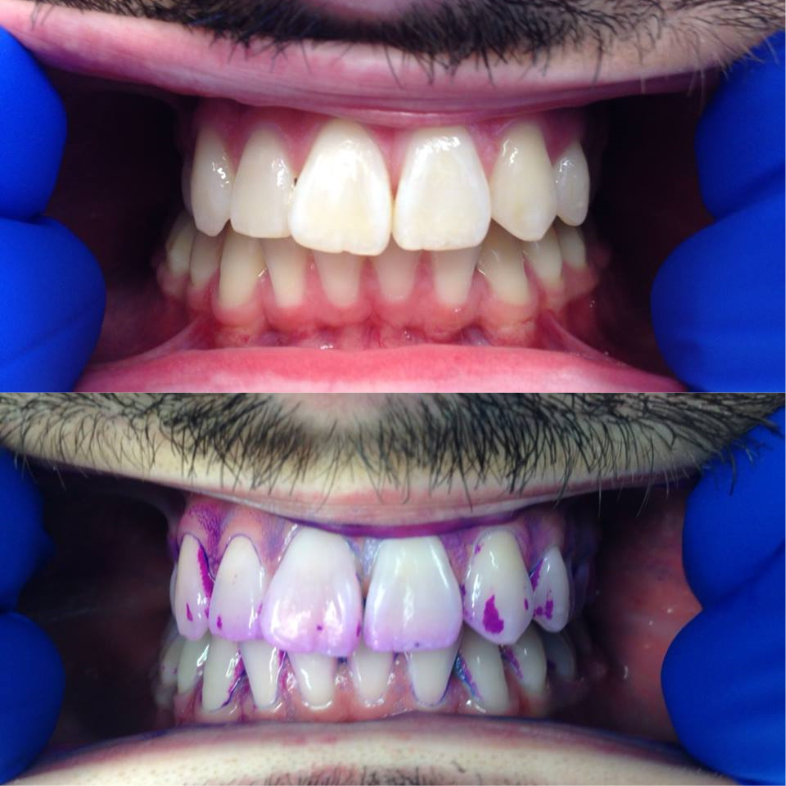

4. 치태의 검출

치태는 육안으로 확인하기 어려울 수 있지만, 치태 착색제(검출 젤 또는 정제)를 사용하면 쉽게 확인할 수 있다. 치태 착색제는 치태가 있는 부위를 붉은색 등으로 착색시켜 보여준다.[1]

치태 검출 제품은 검출제라고도 하며, 치태를 임상적으로 볼 수 있게 해준다. 치아의 깨끗한 표면은 검출제를 흡수하지 않고, 거친 표면만 흡수한다. 치태 검출 젤은 가정이나 치과에서 사용할 수 있다. 이러한 제품에 포함될 수 있는 요오드, 식용 색소 또는 기타 성분에 대한 알레르기가 있는지 일반의와 확인하는 것이 필요하다. 이 젤은 치태 바이오필름의 존재를 평가하는 시각적 보조 수단을 제공하며, 치태의 성숙도도 보여줄 수 있다.

치태 착색제는 치태 착색 젤과 유사하지만, 입 안에 넣고 약 1분 동안 씹어 사용한다는 차이점이 있다. 씹고 남은 정제나 침은 뱉어낸다. 착색 젤은 치태의 존재를 보여주지만, 치태의 성숙도 수준은 종종 보여주지 못한다. 치태 착색제는 최적의 세정을 위해 치아를 닦기 전과 후에 사용하도록 교정 장치를 사용하는 환자에게 처방되거나 제공되기도 한다. 또한 어린 아이나 특정 부위의 치태 제거에 어려움을 겪는 환자에게 유용한 교육 도구이기도 하다. 치태 착색 젤과 정제는 모든 연령대의 개인이 효과적인 치태 제거를 보장하는 데 유용하다.